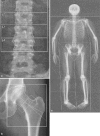

This article reviews dual X-ray absorptiometry (DXA) technique and interpretation with emphasis on the considerations unique to pediatrics. Specifically, the use of DXA in children requires the radiologist to be a "clinical pathologist" monitoring the technical aspects of the DXA acquisition, a "statistician" knowledgeable in the concepts of Z-scores and least significant changes, and a "bone specialist" providing the referring clinician a meaningful context for the numeric result generated by DXA. The patient factors that most significantly influence bone mineral density are discussed and are reviewed with respect to available normative databases. The effects the growing skeleton has on the DXA result are also presented. Most important, the need for the radiologist to be actively involved in the technical and interpretive aspects of DXA is stressed. Finally, the diagnosis of osteoporosis should not be made on DXA results alone but should take into account other patient factors.